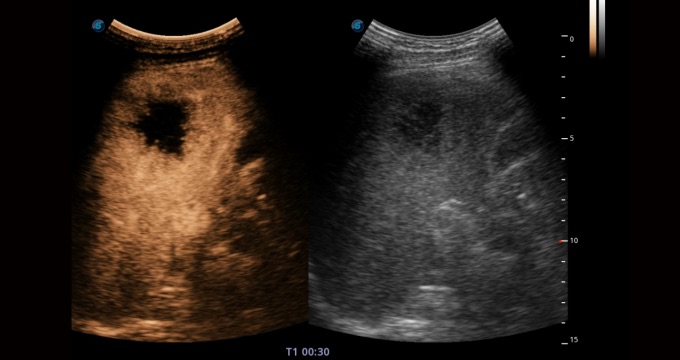

• 造影成像

造影成像功能和定量分析工具包使医生能够更好的评估血流灌注情况。独特的动态声压控制技术可有效控制造影剂的声压,保证更长的造影剂持续时间,更好的观察病变灌注的延迟相位。